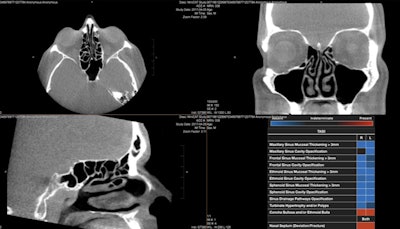

On CT scans, Paranasal Classifier detects and distinguishes between conditions prevalent in the paranasal sinuses, according to InformAI. Its second classifier software -- Brain Cancer Classifier -- spots and characterizes brain cancer on MRI.

InformAI’s lead product – SinusAI – is an AI algorithm that detects and distinguishes several conditions and features prevalent in the paranasal sinuses. Image courtesy of InformAI.In 2020, InformAI was awarded a $225,000 Small Business Technology Transfer grant from the National Science Foundation to build an AI application to assist organ transplant surgeons in the matching of donor organs with patient recipients.